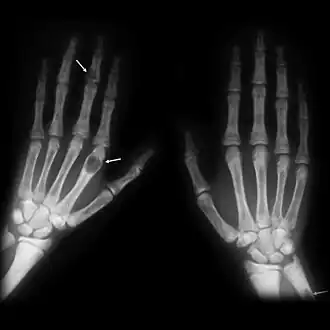

X-ray of the hands showing brown tumors in the long bones of the fingers

X-rays may also be used to diagnose the disease. Usually, these X-rays will show extremely thin bones, which are often bowed or fractured. However, such symptoms are also associated with other bone diseases, such as osteopenia or osteoporosis.[29] Generally, the first bones to show symptoms via X-ray are the fingers.[22] Furthermore, brown tumors, especially when manifested on facial bones, can be misdiagnosed as cancerous.[29] Radiographs distinctly show bone resorption and X-rays of the skull may depict an image often described as "ground glass" or "salt and pepper".[30][31] Dental X-rays may also be abnormal.[2]